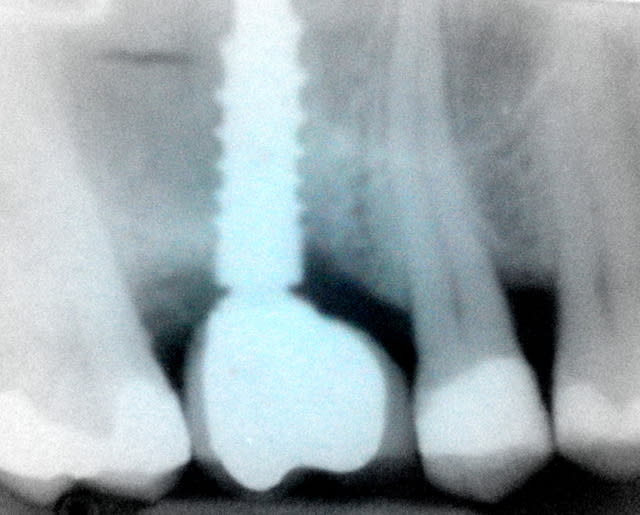

Un patient de 52 ans présente une fracture de racine au site 26.Après division de la racine, extraction de la dent,préparation de la cavité avec un foret conique triangulaire (3 faces,condensation de l´os), puis implantation à 50 Ncm (implant 10mm long, 4,5mm diamètre).Utilisation d´acide hyaluronique pour stimuler la synthèse des ostéoblastes.Pose d´un clip gingival pour préformer la gencive.Après 7 semaines, réalisation d´une empreinte fermée en 5 minutes.Une semaine après, fixation de la couronne définitive ( on observe déjà une ostéointégration).

Bonsoir merci pour ta question, comme tu vois sur la radioDVT il n y avait pas assez de place pour mettre un 6,5mm seulement la racine palatinale était d une longueur de 10/12 mm. Mon premier challenge etait d avoir une premiere stabilité supérieure à 40 Ncm.Le laboratoire est donc important pour que le patient puisse nettoyer facilement la région implantaire.

la radioDVT que j ai oublié de poster

L ossintegration est visible surtout en comparant avec la radio au moment de l implantation. Je cherche la photo pour la joindre.